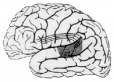

Fluent aphasia with frequent semantic (verbal) paraphasias. Language comprehension, naming and repetition are severely impaired. Fluent aphasia with frequent semantic (verbal) paraphasias. Language comprehension and repetition are severely impaired. Naming is impaired, and in contrast to Broca’s aphasia, prompting provides little benefit. Lesions usually involve the posterior-superior portion of the dominant hemisphere temporal lobe. The lesions are generally vascular.

Ospedale Campo di Marte 2001